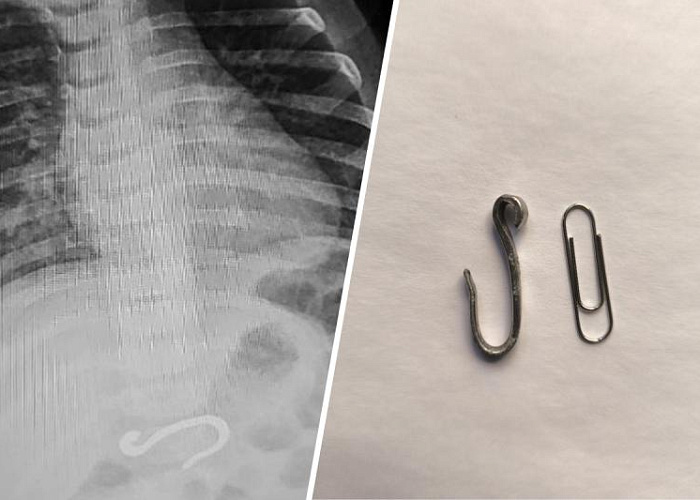

В Челябинске врачи ЧОДКБ столкнулись с необычным случаем, когда восьмимесячному ребенку был обнаружен металлический крючок в желудке. Малыш поступил в экстренный приемный покой с подозрением на проглоченный колпачок от ручки, но рентгеновское обследование показало наличие внушительного железного предмета.

Крюк находился в желудке и частично уже переместился в двенадцатиперстную кишку. Первоначально медики предположили, что это рыболовный крючок, однако форма и размеры предмета не соответствовали. Родители малыша не могли объяснить, как он мог найти этот предмет.

Перед медицинским персоналом стояла задача извлечь крюк без повреждения нежных тканей ребенка. Размер желудка усложнял задачу, но врачи смогли обойтись масочным наркозом. Процедура заняла около часа: сначала крюк переместили в более просторное место, а затем аккуратно извлекли.

Заведующая эндоскопическим отделением Татьяна Лещёва отметила, что перемещение инородного тела в столь маленьком желудке технически сложно. Ширина крючка была значительно больше, чем ребро монеты, и несколько раз он срывался на уровне пищевода, что требовало дополнительной работы по его позиционированию.

К счастью, крюк оказался химически нейтральным и не повредил внутренние органы малыша. Процедура прошла без осложнений, и ребенка быстро выписали домой.